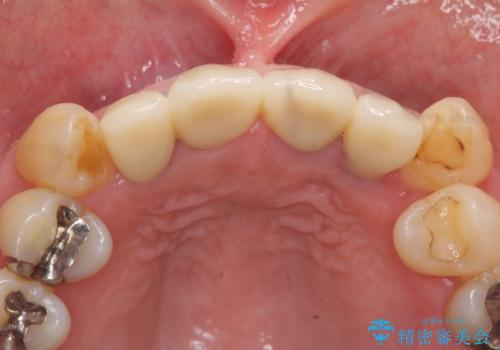

- 52.8万円(ジルコニアクラウン×4・仮歯×4)費用は治療当時の料金となります

オールセラミックによる審美的な仕上がりに満足いただくことができました。